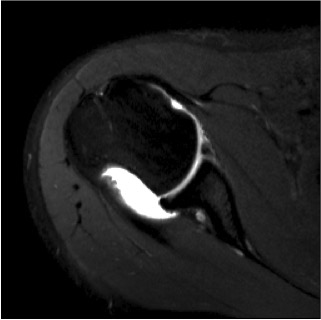

Union

Not all fibrous unions need revision - can result in stable shoulder

Complete bony union of Latarjet

Nonunion / fibrous union

Hardware issues

Screw backout

Intra-articular screw

Osteoarthritis

Nonunion with failure of fixation / recurrent instability

Nonunion with failure of fixation

Latarjet nonunion with hardware failure and displacement of coracoid fragment